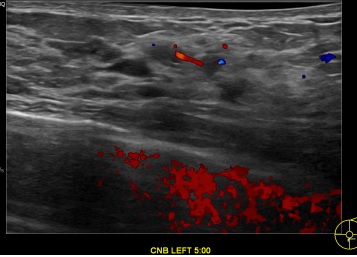

상기환자는 외부검진이상소견  정밀검사위해 내원하신 40대 초반

여성분으로 의심스러운 좌측유방혹 조직검사 시행해 제자리암으로 진단되었습니다